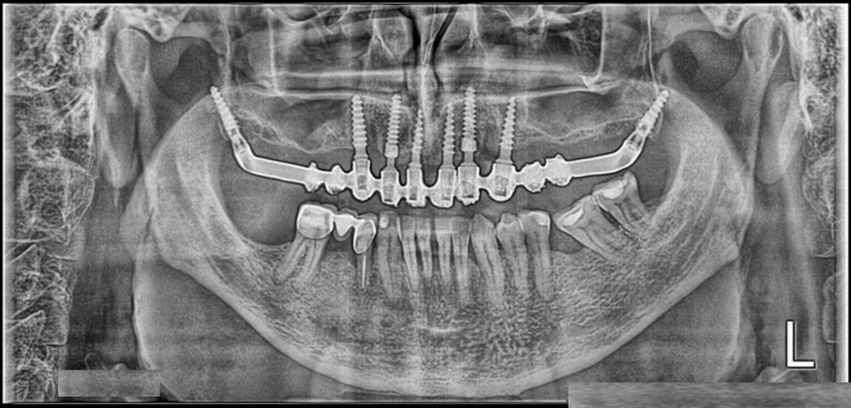

Ортопантомограмма дает четкое, неискаженное по форме изображение зубов. На нем хорошо видны полости, кариозные дефекты, периодонтальные щели, кисты, гранулемы, следы переломов, участки воспалений, опухолевые процессы. Снимок не определяет толщину и наклон альвеолярных отростков, зато отчетливо показывает ход костных балок, очаги резорбции и остеопороза, каналы артерий. Хорошо определяется взаиморасположение корней зубов и имплантатов, высота и ширина зубочелюстных структур. У пациентов с удаленными зубами панорамный снимок объективно отражает процесс восстановления костных структур и перестройку костной ткани.

Благодаря показателям истинной высоты межальвеолярных перегородок, ортопантомограмма дает исчерпывающий диагностический материал при оценке степени генерализованного пародонтита – на снимках четко очерчены участки резорбции, очаги разрушенной ткани. Съемка в динамике очень показательна при определении активности костной деградации, а при направленной тканевой регенерации помогает оценить возможность имплантации и обосновать выбранную тактику лечения.